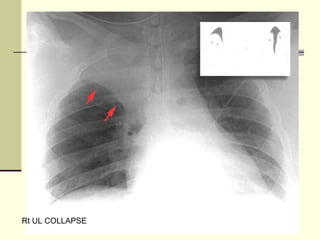

Rt UL COLLAPSE

• 16.

• 17.